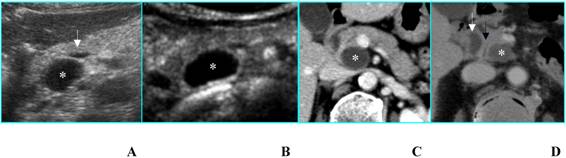

Nonfunctioning islet cell tumor in an asymptomatic 80-year-old woman. A. B-mode US shows a 2-cm hypoechoic nodule (calipers) located in the uncinate process of the pancreas. B. On CEUS the nodule is hyperechoic (asterisks) in the portal phase. C. Axial CT image depicts the same nodule as hyperdense in the venous phase (arrow).

b) Islet cell tumors- functioning or nonfunctioning – are usually hyperechoic in the arterial phase (enhancement superior to normal pancreatic parenchyma) because of their rich vascularization [8]; after the enhancement a rapid washout of the lesion is appreciable, resulting in a slightly hypoechoic appearance during the venous phase [8]. Sometimes, enhancement is more important in the portal phase (Fig. 3), similarly to what has been reported for dynamic studies performed with CT [9]. In addition, in huge nonfunctioning islet cell tumors, enhancement may be heterogeneous due to necrosis or cystic degeneration [8].

c) Serous microcystic adenomas (SMAs) sometimes show at B-mode US a hypoechoic “solid-appearing” pattern, due to submacroscopic size of the cysts [10] (Fig. 4A); these tumors can be properly characterized by CEUS that demonstrates the typical honeycomb pattern (Fig. 4B), as well as by MR [11] (Figs. 4C and D).

Serous microcystic adenoma in an asymptomatic 66-year-old woman. A. B-mode US shows a hypoechoic mass (calipers) located in the head of the pancreas. B. On CEUS the lesion has a honeycomb appearance (asterisks), typical of serous microcystic adenoma. C. Axial T2-weighted MR image shows a hyperintese lesion made up of cluster of microcysts. D. Axial gadolinium-enhanced fat-suppressed T1-weighted MR image depicts the honeycomb appearance with enhancement of thin septa.